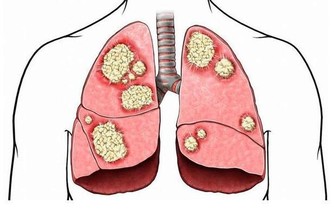

第5名:不愛喝水

如果長時間不喝水,尿量就會減少,尿液中攜帶的廢物和毒素的濃度就會增加,容

易引發腎結石等,建議每天至少喝水1200~1500毫升。

第6名:海鮮+啤酒

很多人喜歡就海鮮喝啤酒。

海鮮產品是高蛋白食物,含有嘌呤和苷酸成分,和啤酒混合在一起,會產生過多的尿酸和尿素氮等代謝物,

加重腎臟負擔,易導致高尿酸血症,甚至腎結石、尿毒症。

第7名:常喝濃茶

茶葉中含有咖啡因,少量可起到醒神作用,如果攝入過多會使血流加快、血壓升高。

體內經常含有較高濃度的咖啡因,會對腎臟帶來巨大負擔。

此外,茶葉中含有較多鞣酸,容易和與體內的鐵結合變成一種難溶性物質,可致腎結石。

第8名:過度喝飲料

軟飲料和運動飲料的過度攝取會間接損傷腎。人體內的酸鹼度為7。

這些飲料普遍為高度酸性,飲用後體內酸鹼度明顯改變。

第9名:整天大魚大肉

蛋白質是人體必需的營養素,重視蛋白質的攝取是應該的,但這不代表“高蛋白食物吃得越多越好”。

健康人群通過均衡飲食,就足以補充每日所需的蛋白質。

但現在很多職場人士經常應酬,大魚大肉,導致蛋白質攝入量超標。

長期的高蛋白攝入會增加腎臟負擔,甚至使腎臟長期處於“超負荷”狀態。